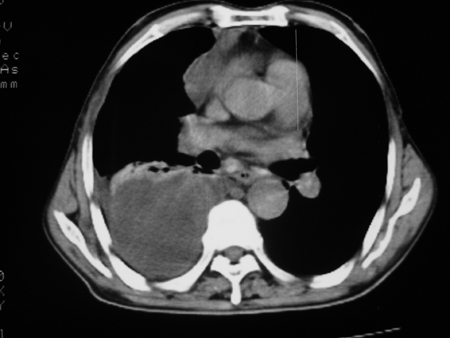

男77岁,胸痛就诊

右侧胸腔积液,部分包裹,右下肺膨胀不全,右下肺感染。

考虑右肺门占位并下叶不张 右胸包裹积液

右肺中叶及下叶炎症并胸腔积液(部分包裹),建议抽液后复查ct除外占位。